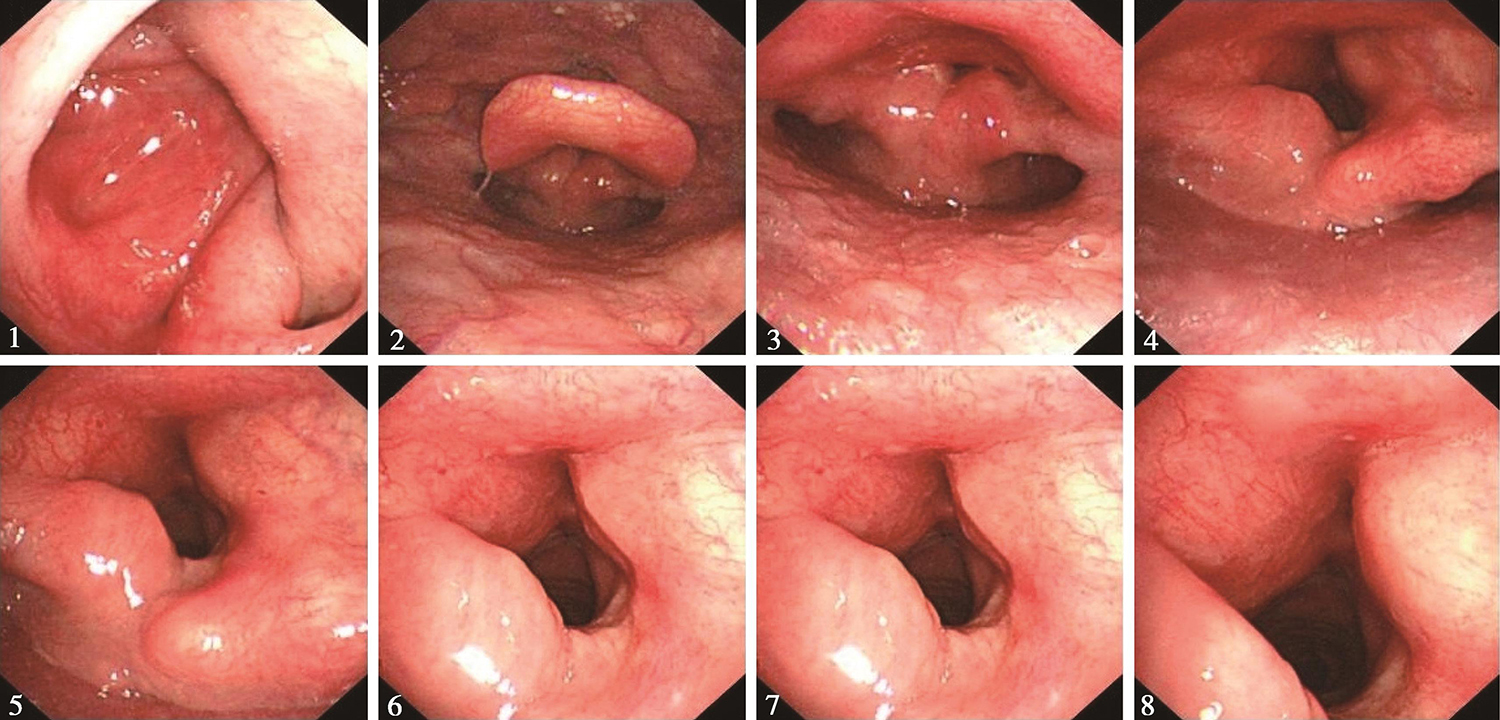

5.2016年8月25日电子鼻咽喉镜检查

“喉癌术后1年余”,鼻腔进镜顺利。鼻咽部结构完整,黏膜光滑,未见明显异常。口咽双侧扁桃体未见肿大。舌根部淋巴滤泡增生明显。下咽部表面基本平整,未见明显异常。喉部声门上结构基本完整,双侧披裂保留,略显水肿。声门区左侧声带切除,局部基本平整,声门区未见明显肿瘤征象。左半喉基本固定,右半喉活动尚可(图5)。

图5 2016年8月25日复查喉镜示声门区未见明显肿瘤征象

内镜诊断:

喉癌术后,左侧声带切除,残喉未见明显肿瘤复发征象。

9.2017年4月21日电子鼻咽喉镜

“喉癌术后2年”,鼻腔进镜顺利。鼻咽部结构完整,黏膜光滑,未见明显异常。口咽双侧扁桃体未见肿大。舌根部淋巴滤泡略增生。下咽部表面基本平整,未见明显异常。喉部声门上结构基本完整,双侧披裂保留,略显水肿。声门区左侧声带切除,局部基本平整,声门区未见明显肿瘤征象。左半喉活动度小,右半喉活动尚可(图6)。

图6 2017年4月21日复查喉镜

喉癌术后,声门区呈术后改变,残喉同前相仿,未见肿瘤复发征象。